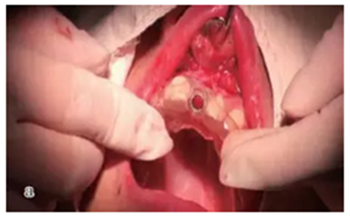

逐級備孔

戴上導(dǎo)板逐級備孔,然后植入種植體,旋入覆蓋螺絲。

注意導(dǎo)板的就位要準(zhǔn)確不晃動,備孔時(shí)應(yīng)充分冷卻。

圖11 導(dǎo)板上備孔并植入植體,a.戴上導(dǎo)板,逐級備孔;b.植入種植體,并旋入覆蓋螺絲